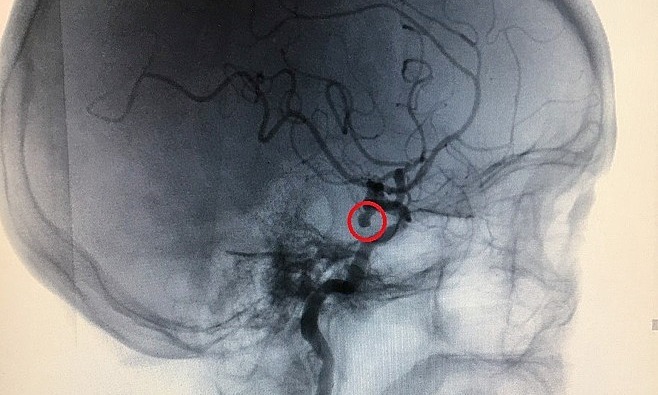

Bác sĩ Nguyễn Thị Nhã, Giám đốc Trung tâm Hỗ trợ Sinh sản, chỉ định phân tích karyotype của bệnh nhân xét nghiệm. Kết quả cho thấy cô có hai nhiễm sắc thể số 21 liên kết với nhau. Đây là bất thường nhiễm sắc thể phổ biến nhất, gây ra bệnh Down ở 1 trong 700 trường hợp.

Trẻ mắc bệnh Down thường có trí tuệ nhẹ, thông minh và trí tuệ. — Bác sĩ Nhã nhấn mạnh: “Trong trường hợp bất thường này, người mẹ sẽ sinh ra đứa trẻ có bộ nhiễm sắc thể số 21 bất thường gây ra bệnh Down”